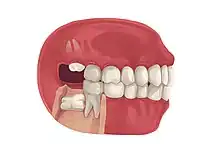

Impacted wisdom teeth are often described by the direction of their impaction (forward tilting, or mesioangular being the most common), the depth of impaction and the age of the patient as well as other factors such as pre-existing infection or the presence of pathology (cysts, tumors or other disease).[5]: 143–144 Each of these factors is used to predict the difficulty (and rate of complications) when removing an impacted tooth, with age being the most reliable predictor[8] rather than the orientation of the impaction.[9]

Impacted wisdom teeth are classified by the direction and depth of impaction, the amount of available space for tooth eruption, and the amount of soft tissue or bone (or both) that covers them. The classification structure helps clinicians estimate the risks for impaction, infections and complications associated with wisdom teeth removal.[6] Wisdom teeth are also classified by the presence (or absence) of symptoms and disease.[7]

| Types | Full vs partially impacted, direction of impaction |